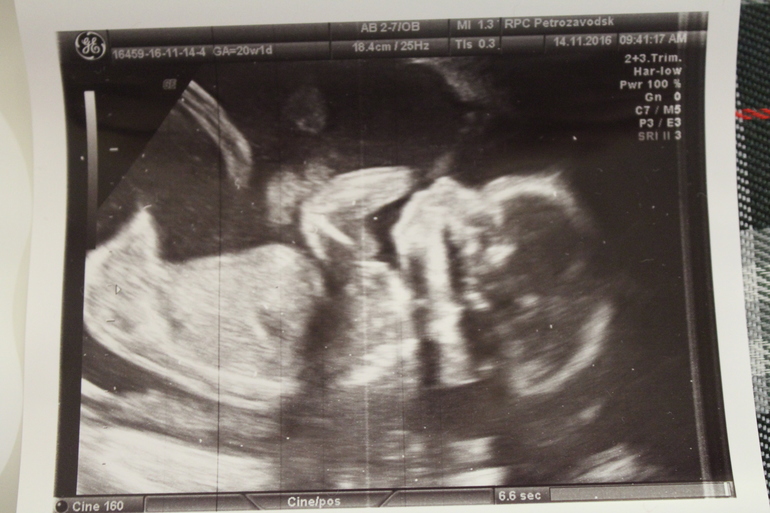

20 нед.+1 2УЗИ

❤️2ая БПриехала только что с узи)

Все отлично,соответствуем сроку) Малышка буянила,пинала датчик ,отворачивалась,а потом сладко зевнула и уснула). Девочка осталась неизменной)

Ну и фото)